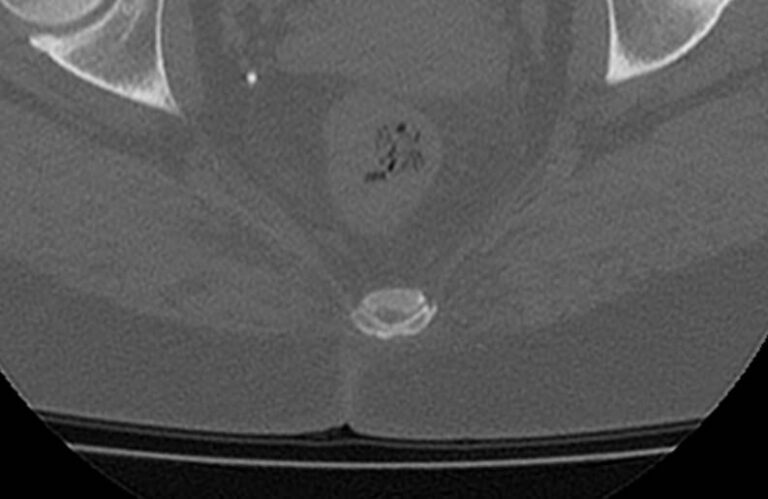

Для диагностики даже незначительных патологических изменений в различных отделах позвоночника, особенно в случае распространенного поражения, применяется один из современных наиболее информативных методов обследования – мультиспиральная компьютерная томография всего позвоночника. Методика основана на использовании проникающей способности рентгеновских лучей через органы и ткани человека и позволяет получить подробное изображение всех структур позвоночного столба. В комплексное обследование входит исследование шейного, грудного, пояснично-крестцового отделов позвоночника и копчика.

- стеноз (сужение) позвоночного канала;

- грыжи межпозвонковых дисков (протрузии, экструзии и грыжи Шморля);